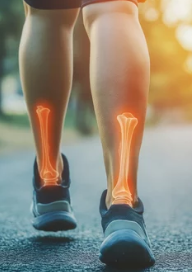

오금(슬와부)은 무릎 뒤쪽에 위치한 부위로, 인대, 근육, 신경 등이 복잡하게 얽혀 있습니다.

이 부위에서 통증이 발생하면 걷기, 계단 오르기, 무릎을 구부렸다 펼 때 불편함을 유발할 수 있습니다.